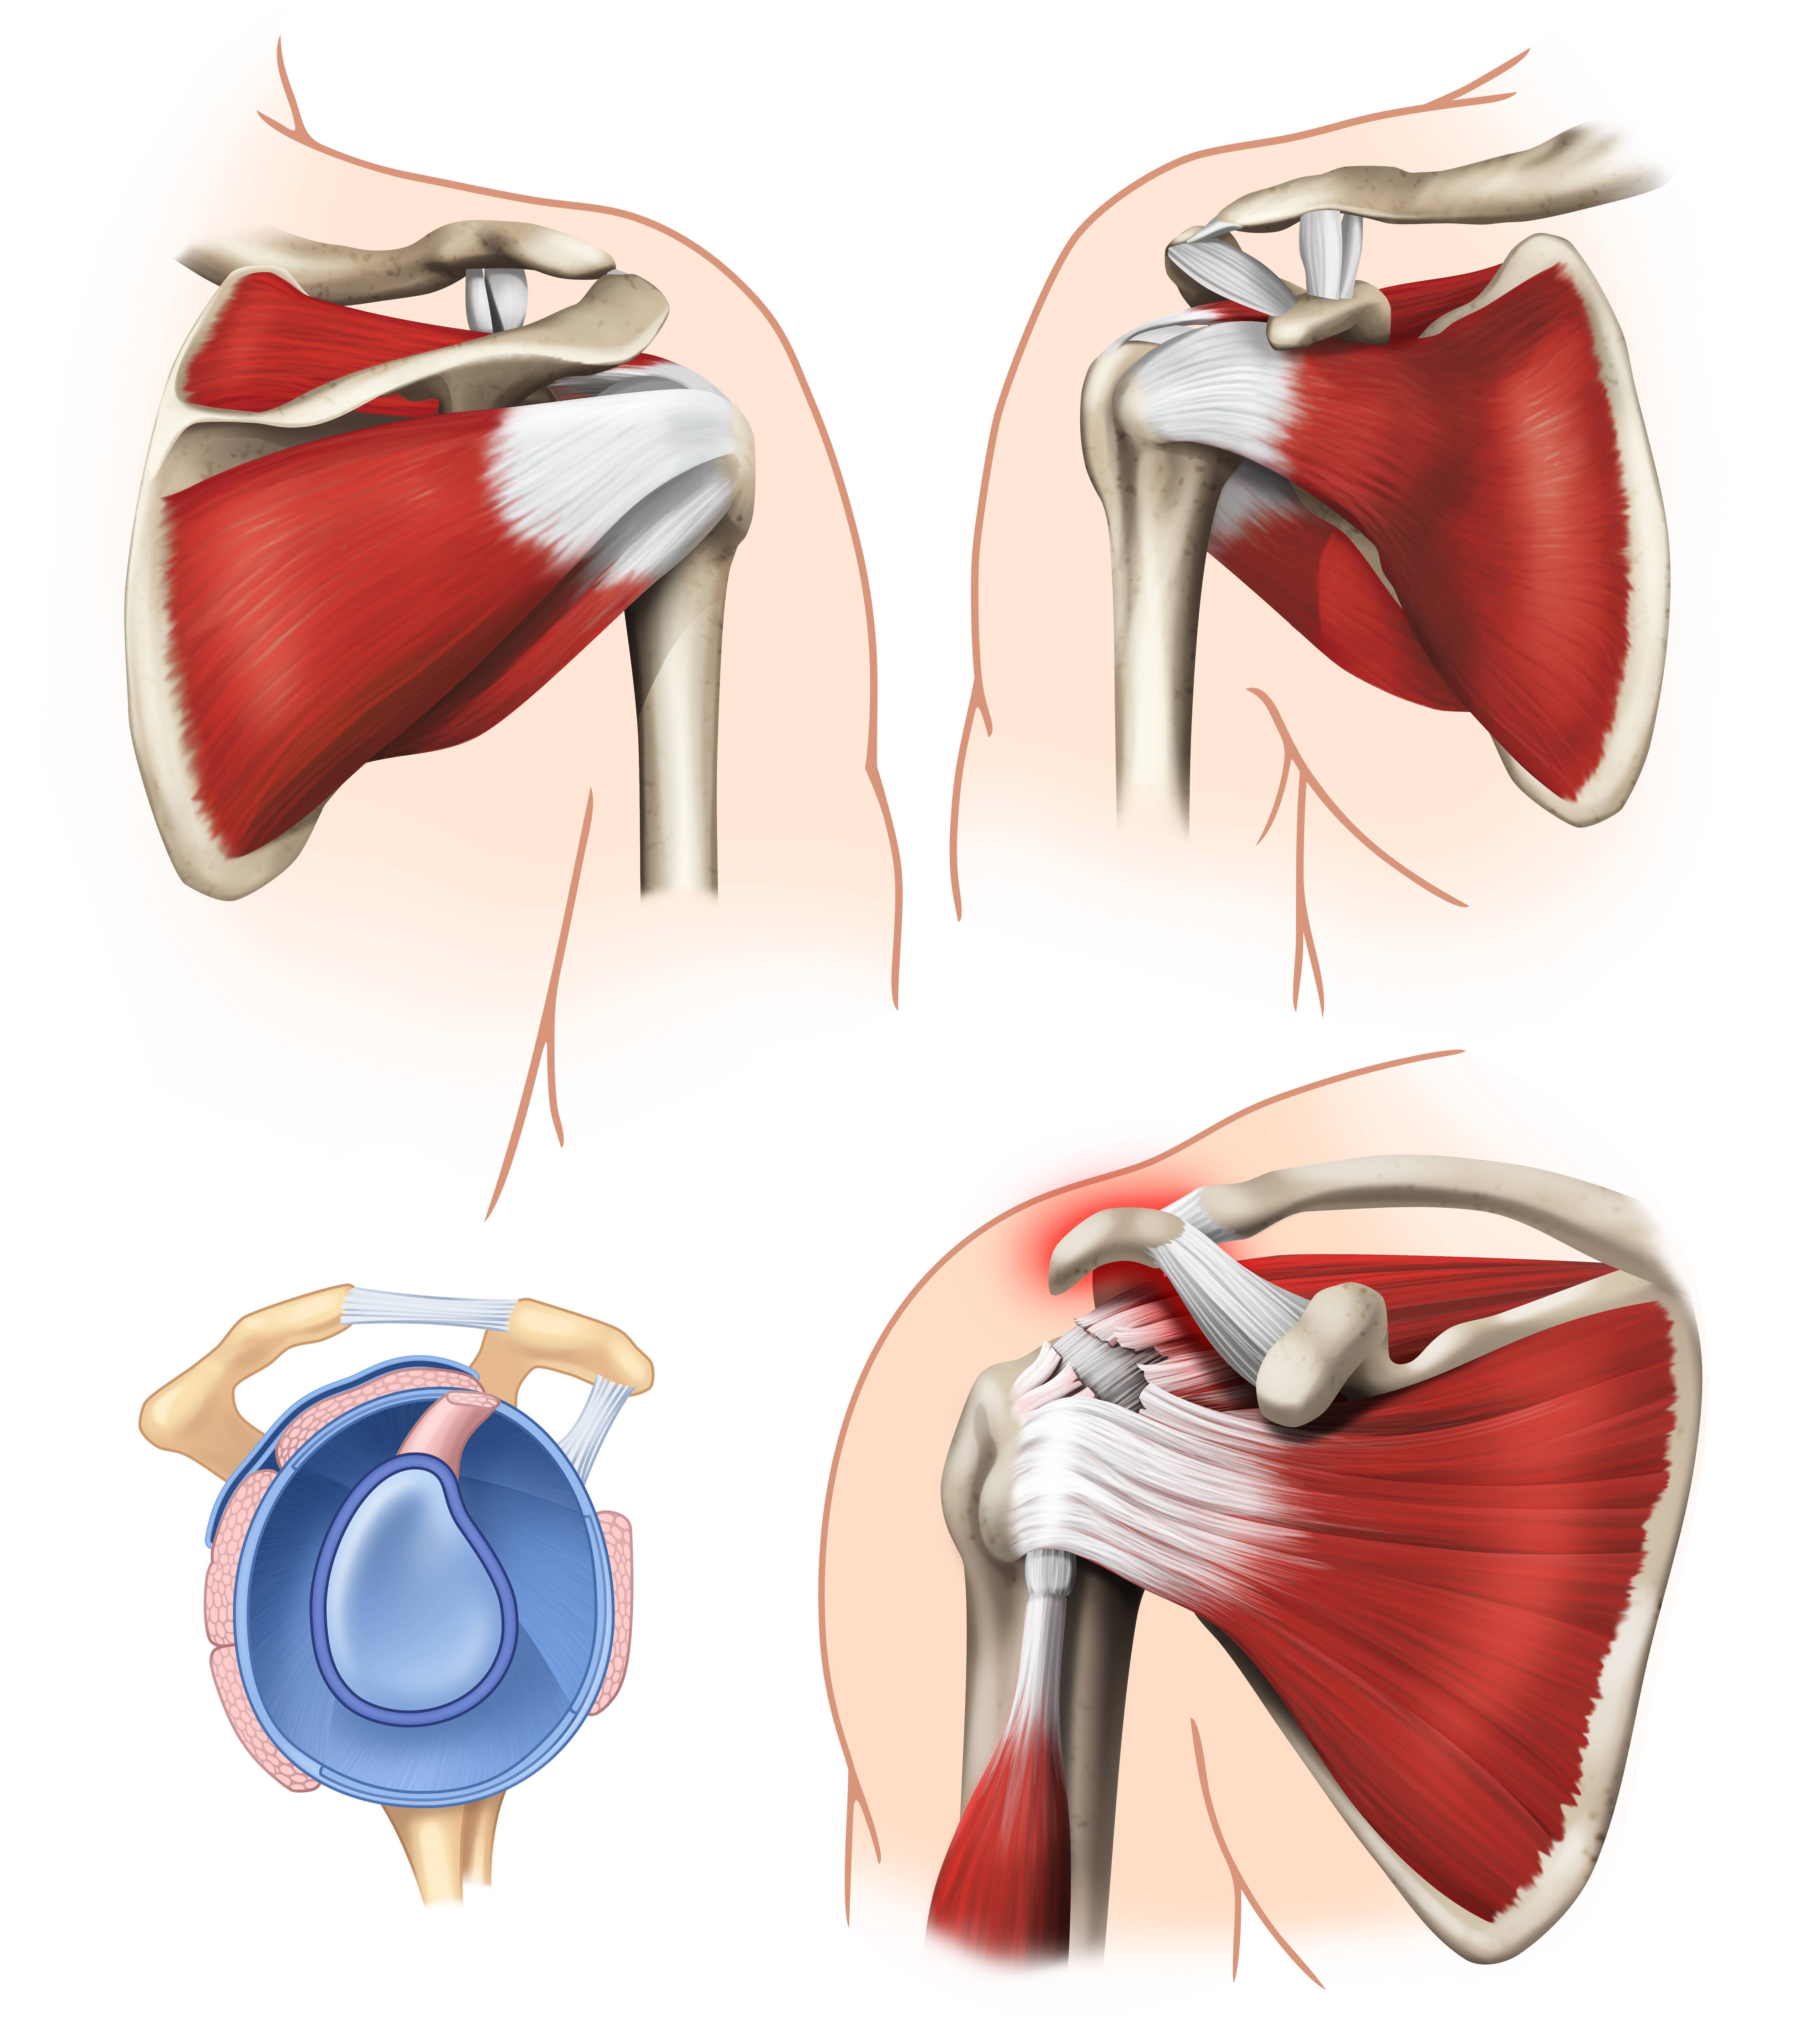

Фотографии мышц ротаторной манжеты плеча